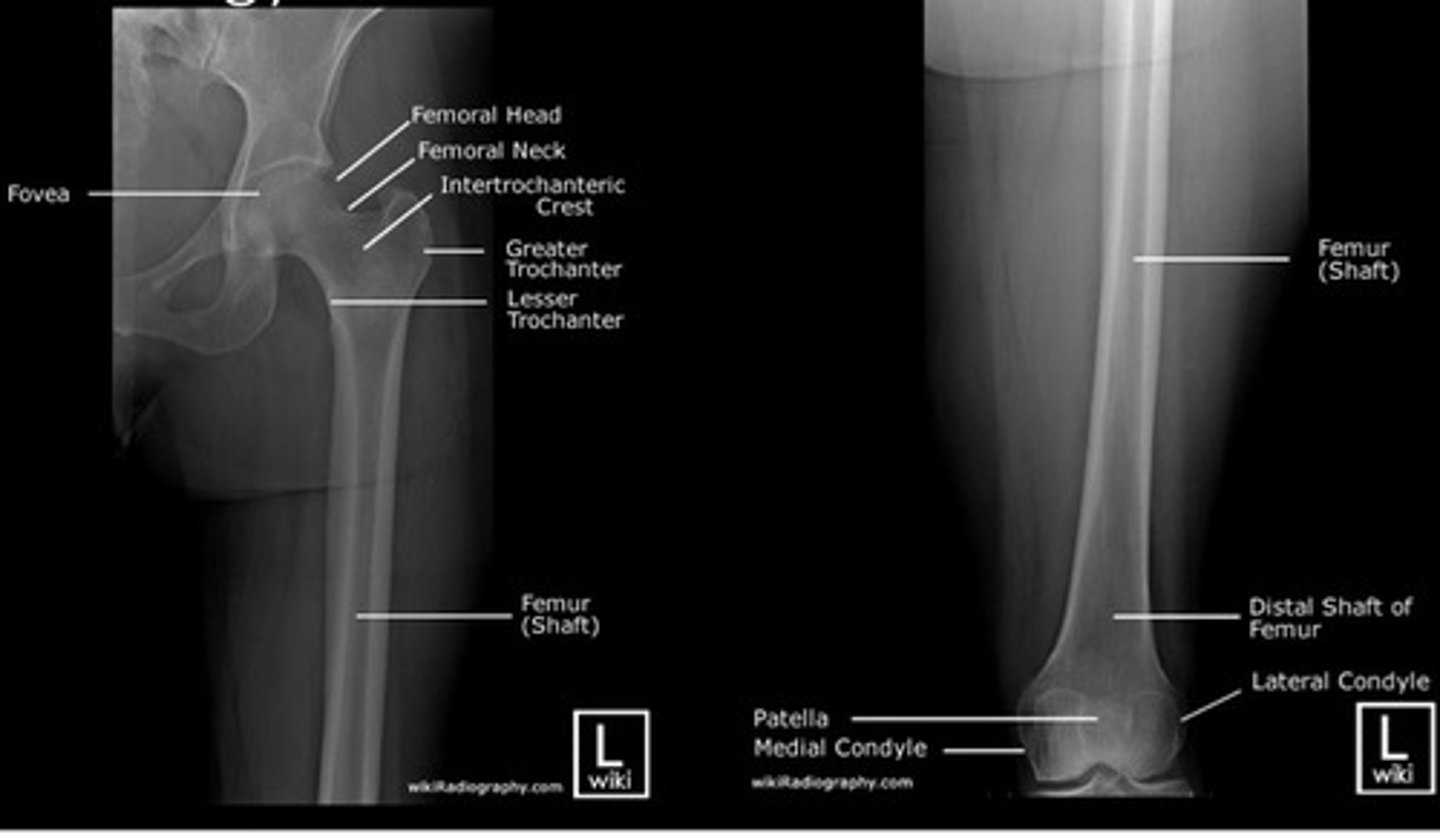

What are the main basic projections for imaging of the FEMUR?

- Antero-posterior (AP)

- Lateral

What are appropriate clinical indications for plain radiography of the femur?

- Trauma

- Pain

- Arthritis (Rheumatoid & Osteoarthritis)

- Foreign body

How should we COLLIMATE when doing an AP FEMUR projection? What structures should be included in the image?

- to include the entire length of the femur and soft tissue borders. The knee and hip joint must be included.

- to include the entire length of the femur and lateral soft tissue borders. The knee and hip joint must also be included.

State the criteria for assessing the radiographs of the knee, femur, tibia & fibula.